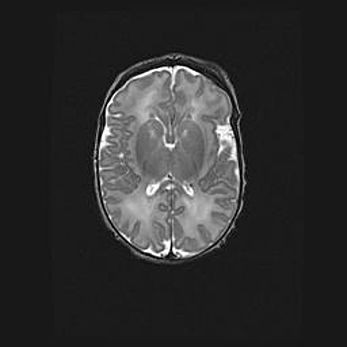

Множественные кисты обоих полушарий головного мозга, наибольшая из них в правой затылочной области. Ассиметричная атрофическая гидроцефалия.

Возраст: 7 месяцев

Вес: 5660 г

Пол: мужской

Окружность головы: 41,5 см

Срок гестации: 28-29 недель

Кисты головного мозга развиваются в результате многоочаговых некрозов вещества мозга и возникают вследствие перенесенной перинатальной инфекции, менингитов, энцефалитов, асфиксии, родовой травмы, расстройств мозгового кровообращения различного генеза. Образованию кист в веществе головного мозга плодов и новорожденных способствуют такие факторы, как высокое содержание в нем воды, недостаточная (или отсутствие) миелинизация и слабая астроглиальная реакция на повреждение.

Кисты могут сочетаться с гидроцефалией и другими поражениями головного мозга.